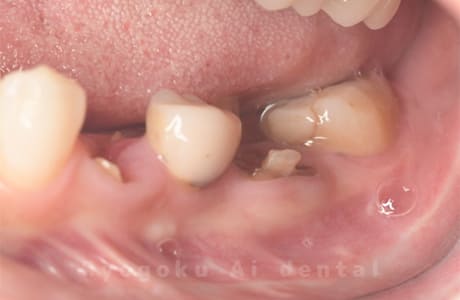

Case14

- 抜歯原因

- 重度カリエス

- 治療内容

- クラウンレングスニング治療

- 治療費用

- 44,000円

他院で抜歯と言われた、とのことでご来院された患者さまです。クラウンレングスニングを行い、保存致しました。大変満足して頂けました。